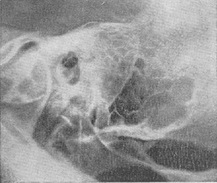

Рентгенологічна картина початкової, ексудативної форми мастоидита характеризується затемненням клітин; симптоми кісткової деструкції відсутні. У наступній фазі мастоидита на рентгенограмі виявляється значна втрата інтенсивності тіней перегородок клітин, місцями майже повна відсутність їх зображення, що пояснюється розсмоктуванням кісткової тканини відростка. Гнійне розплавлення перегородок клітин з утворенням абсцесу в сосцевидном відростку визначається рентгенологічно у вигляді вогнища розрідження. Цей симптом вторинного просвітлення виникає, незважаючи на присутність в порожнині абсцесу гнійної рідини, внаслідок руйнування кісткової тканини, поглинає промені (рис. 1).

Вогнище деструкції кісткової може мати деякий час трабекулярное будова через збережених клітин, що оточують порожнину абсцесу. Томографія скроневої кістки дозволяє виявити в цій фазі гнійник. При утворенні субпериостального абсцесу з повним руйнуванням кістки виникає інтенсивне гомогенне просвітлення (рис. 2 і 3). Велика солітарна клітка в сосцевидном відростку - відносно рідкісний анатомічний варіант (рис. 4 і 5) - при гострому отиті може вести до неправильної рентгенодіагностиці мастоидита, особливо його латентної форми, при бідному клітинами сосцевидном відростку. Порожнину такий клітини помилково приймається навіть за холестеатому (рис. 6), що потрапив у соскоподібний відросток. Наявність периантральных клітин вказує на анатомічний варіант, але не на вушну холестеатому, завжди сполучається з холестеатомной порожниною в антруме.

Для виявлення затемнених периантральных клітин і холестеатомной порожнини в області антрума слід користуватися проекцією Майєра. Порожнину субпериостального абсцесу, якщо вона не утворилася з кількох великих клітин (рис. 7), як правило, не має чітких обрисів, властивих холестеатоме. Верхівковий мастоїдит (абсцес Бецольда) можна не виявити, якщо обмежитися однією лише проекцією Шюллер. Рентгенограма по Стенверсу дозволяє виявити дефект внутрішньої кортикальної пластинки соскоподібного відростка (рис. 8-10).

Рис. 1. Рентгенограма скроневої кістки за Шюллеру; гострий мастоїдит; затемнені клітини, великий деструктивний вогнище в сосцевидном відростку (симптом вторинного просвітлення).

Рис. 2. Гострий мастоїдит, великий кістковий дефект в сосцевидном відростку; субпериостальный абсцес (права скронева кістка). Рис. 3. Ліва скронева кістка (норма) - порівняльна рентгенограма.

Рис. 4 і 5. Рентгенограми нормальної скроневої кістки (рис. 4 - проекція Шюллер; рис. 5 - коса проекція соскоподібного відростка по Стенверсу). Велика солітарна клітина верхівки соскоподібного відростка з тонким лінійним тіньовим контуром. Рис. 6. Порожнину холестеатоми на верхівці відростка з тонким лінійним тіньовим контуром; клітини відсутні (проекція Шюллер).